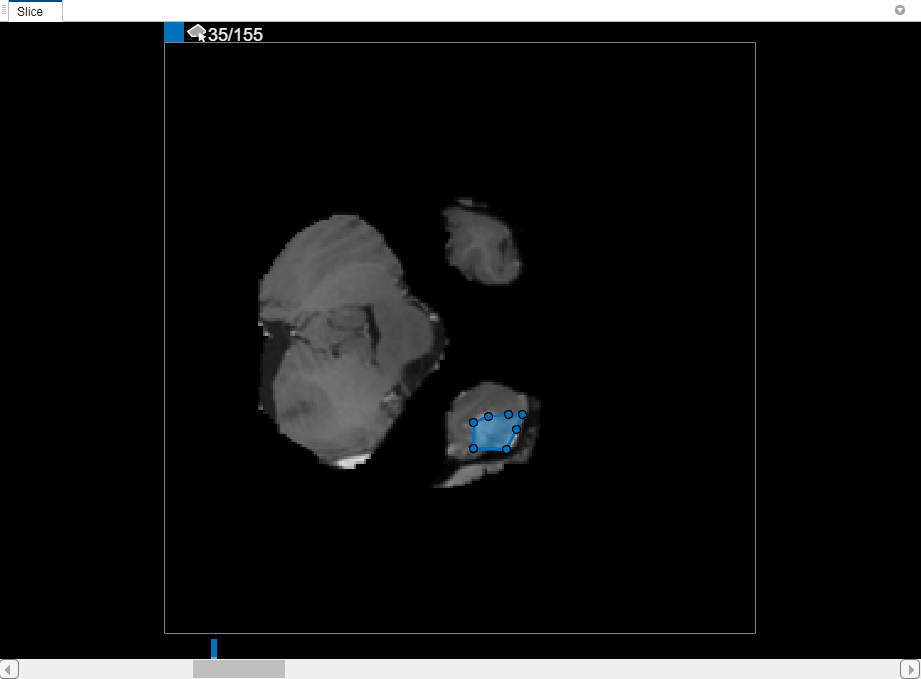

In the Slice pane, navigate to the slice where the object first appears, slice 35, and draw an outline around the object. For this example, use the Polygon drawing tool. Click to create a vertex, then move the cursor and click again to create a second vertex with a straight line connecting them. Continue this process to create a connected line. To add additional vertices after you finish drawing, double-click on the ROI edge.

CreateBinaryMaskUsingVolumeSegmenterExample_05.png